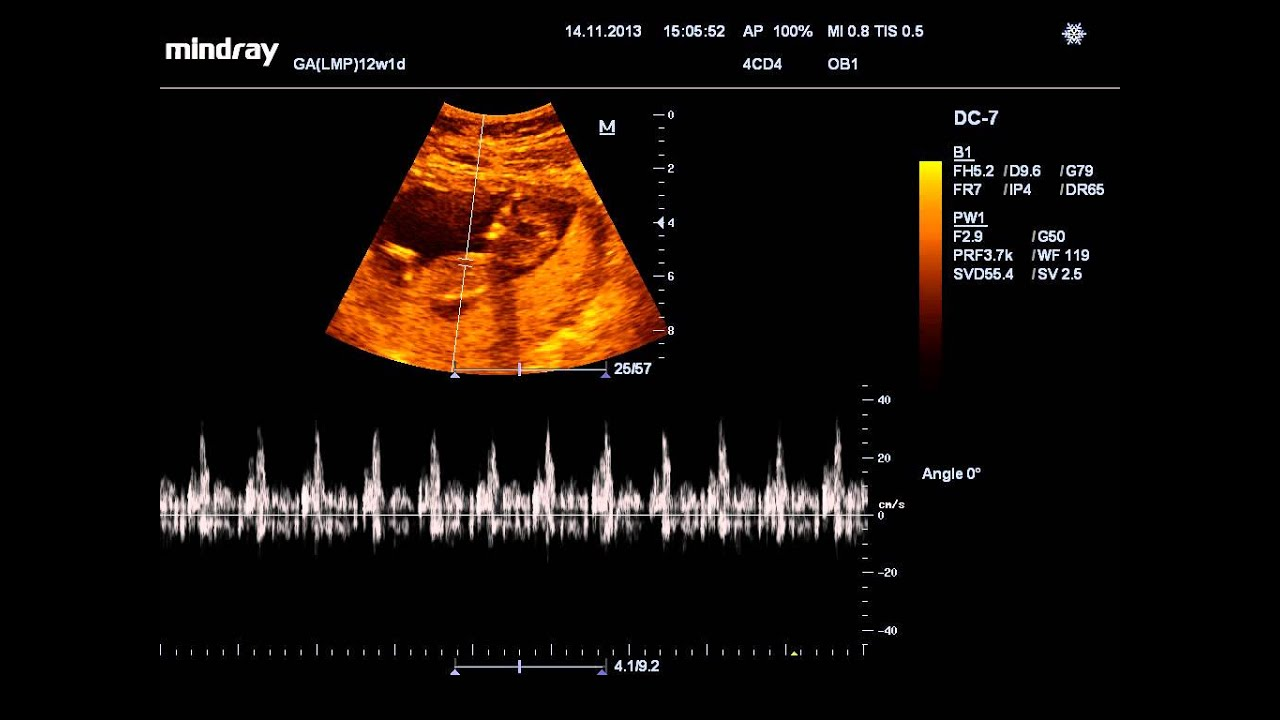

УЗИ на 32 неделе позволяет произвести диагностику и анализ работы сердца плода. Оценивается частота сердечных сокращений, а также их ритмичность.

Эти результаты дадут представление о настоящем состоянии ребенка, правильно ли он развивается и соответствует ли срокам его развитие.